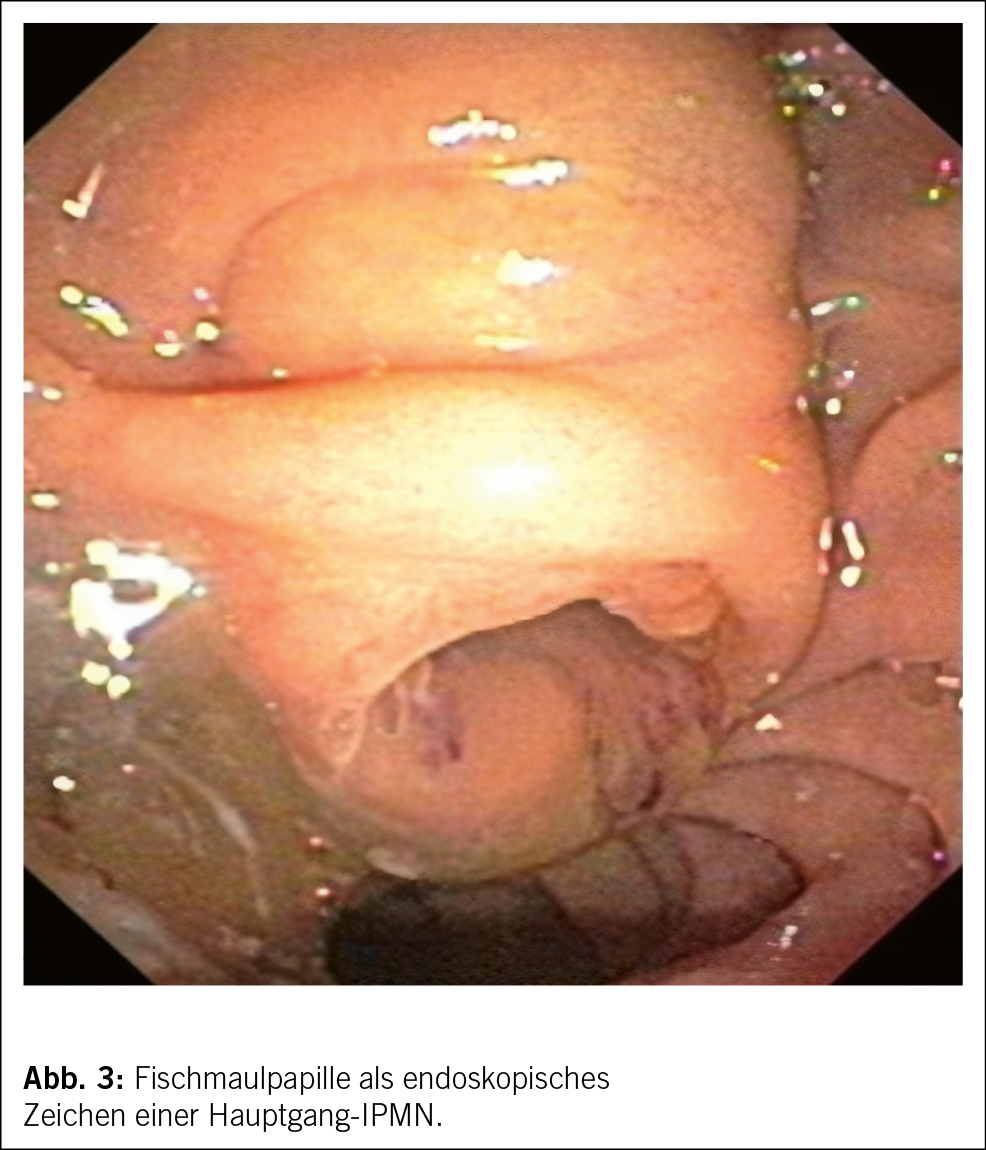

Aus klinischer Sicht stellt sich zunächst die Frage, wie hoch das maligne Potenzial der inzidentell nachgewiesenen zystischen Pankreasläsion zu beziffern ist. Während nicht neoplastische Entitäten wie Pseudozysten oder dysontogene Zysten keinerlei malignes Potenzial aufweisen, handelt es sich bei der Mehrheit der zufällig nachgewiesenen zystischen Pankreasläsionen um neoplastische Zysten respektive Präkanzerosen (Tab. 1). Dementsprechend steht in unserem Beispiel differenzialdiagnostisch eine neoplastische Zyste im Vordergrund, weshalb als nächster Schritt ein MRI durchgeführt wird (Abb. 1a/b), welches eine Verbindung der Läsion zum Gangsystem nachweist. Infolgedessen besteht der dringende Verdacht auf eine Seitenast-IPMN. Aufgrund der Grösse des Befundes entscheidet man sich ferner zur Durchführung einer oberen Endosonographie inkl. Kontrastmittelgabe, wo Noduli definitiv ausgeschlossen werden können (Abb. 1b). Die Analyse der endosonographisch gesteuerten punktierten Zystenflüssigkeit (hohes CEA, hohe Amylase, tiefe Glucose) lässt die Diagnose einer Seitenast-IPMN definitiv stellen. Aufgrund des erhöhten Risikos für die Entwicklung eines Pankreaskarzinoms wird die Aufnahme in ein Surveillance-Programm empfohlen.

Bei der Seitenast-IPMN handelt es sich mit ca. 80 % aller zufällig nachgewiesener zystischer Pankreasneoplasien um die häufigste Entität (2). Das maligne Potenzial hängt von verschiedenen Parametern ab. Wichtigste Kriterien diesbezüglich stellen die Grösse der Läsion, Dilatation des Hauptganges sowie Noduli dar. Hierauf basierend erfolgt eine Risikostratifikation, welche für die weitere Beratung der Patientinnen und Patienten essenziell ist. Diesbezüglich stellt die Arbeit von Mukewar et al. (3) die Verhältnisse sehr anschaulich dar. Während das Risiko eines Pankreaskarzinoms bei einer IPMN mit Hauptgangbeteiligung oder Nodulus als hoch zu bezeichnen ist (ca. 25 %/10 Jahre), ist das Risiko für Patienten mit Seitenast-IPMNs ohne weiterer radiologischer oder klinischer Risikofaktoren deutlich kleiner, relativ zur Normalbevölkerung jedoch immer noch deutlich erhöht (ca. 8 %/ 10 Jahre) (4), wobei das Risiko über die Jahre kontinuierlich ansteigt. Aufgrund der daraus abzuleitenden Indikation zur langfristigen Überwachung ist eine zweifelsfreie Diagnose essenziell. Insbesondere gutartige seröse Zystadenome (Abb. 1c/d) oder inzidentell nachgewiesene Pseudozysten müssen bildgeberisch oder ggf. auch mithilfe einer endosonographisch gesteuerten Punktion ausgeschlossen werden, damit unnötige, repetitive Verlaufskontrollen verhindert werden.

Im Folgenden sollen die typischen bildgebenden Eigenschaften der häufigsten zystischen Pankreasneoplasien (Tab. 1) beschrieben werden. Die bereits oben erwähnte intraduktale papilläre muzinöse Neoplasie (IPMN) kann sich in drei verschiedenen Formen manifestieren, als Seitengang-, als Hauptgang-IPMN oder als gemischte Form. Sie stellt sich als zystische (T2-hyperintense) Dilatation der besagten Gänge dar, d. h. bei Befall der Seitengänge als uni- oder mulitlokuläre, lobulierte, traubenartige Läsion, bei Befall des Hauptgangs in Form als segmentale oder diffuse Dilatation des Pankreashauptganges ≥ 5mm. Ein spezifisches bildgebendes Kriterium, das die IPMN von den anderen zystischen Neoplasien unterscheidet, ist die nachweisliche Verbindung zum Gangsystem (Abb. 1a). Eine typische Eigenschaft der Seitengang-IPMN ist ausserdem die Multiplizität.

Die muzinös-zystische Neoplasie (MCN) tritt fast ausschliesslich bei Frauen auf, mit höchster Inzidenz in der 5. Dekade. Klinisch ist das Erkennen dieser Entität wichtig, da diese Läsionen ein mit der Hauptast-IPMN vergleichbares Malignitätsrisiko aufweisen (9, 10). Die Lokalisation ist häufig im Pankreascorpus oder -cauda. Eine Kommunikation zum Ductus pancreaticus besteht, im Gegensatz zu den IPMN, nicht. Bildmorphologisch besteht meistens eine uni- oder multilokuläre Makrozyste (> 2cm) mit oder ohne Septierungen, teils mit «Zyste-in-Zyste»-Aspekt. Die äussere Begrenzung ist meistens rund, im Gegensatz zur eher lobulierten Seitengang-IPMN. In 25 % finden sich murale Verkalkungen.

Die serös-zystische Neoplasie (SCN) (Abb. 1c/d) kann sich in Form verschiedener Phänotypen manifestieren. Der typische Aspekt ist allerdings der mikrozystische (Zysten < 2 cm) oder Honigwaben-Aspekt. Die Zysten sind oft so klein, dass in der CT der Eindruck einer soliden Läsion entsteht. Ausserdem typisch ist eine zentrale, manchmal verkalkte Narbe, welche sich computertomographisch bestätigen lässt. Erschwerend kommen in ca. 10 % auch atypische, rein makrozystische Formen der SCN vor, welche bildgebend nicht von einer muzinösen Läsion mit Malignitätspotenzial unterschieden werden können.

Die solid-pseudopapilläre Neoplasie (SPN) ist eine seltene Läsion und kommt fast nur bei jungen Frauen in der 2.–3. Dekade vor. Es handelt sich hier um eine gemischt solid-zystische Neoplasie mit Nekrosen und hämorrhagischen Anteilen, typischerweise in der Cauda lokalisiert. Sie sind meist asymptomatisch und werden als Zufallsbefund in der Schnittbildgebung entdeckt.

Bei Pseudozysten handelt es sich typischerweise um hypodense zystische Läsionen mit flächigem Kontakt zum Pankreas. Die Wand der Pseudozyste ist in der Regel zart. Im MRI lässt sich im Gegensatz zur Seitengang-IPMN keine Verbindung zum Gangsystem nachweisen. Nebst der Anamnese mit St. n. Pankreatitis ist das Aspirat des Zysteninhalts charakteristisch, in dem die Amylase bei gleichzeitig tiefem CEA stark erhöht ist (Tab. 1).

Nebst der Charakterisierung einer zystischen Pankreasläsion ist es auch Aufgabe der Radiologie, nach bildgebenden Zeichen zu suchen, welche auf ein erhöhtes Malignitätsrisiko weisen. Diese bildgebenden Zeichen werden in verschiedenen Leitlinien meist in einem zwei- oder mehrstufigen System abgebildet. In den European evidence-based guidelines on pancreatic cystic neoplasms (11) werden bei radiologisch vermuteter IPMN folgende bildgebende Zeichen als «relative Indikation für Chirurgie» bezeichnet (Abb. 2): Wachstumsrate der zystischen Läsion von ≥ 5 mm/Jahr, eine Dilatation des Pankreashauptganges von 5–9.9 mm, Zystendurchmesser von ≥ 4 cm und kontrastmittelaufnehmende murale Knoten von < 5 mm.

Fokussiert zur Differenzierung der benignen Zysten SCA, MCA und IPMN kann die Punktion mit Bestimmung CEA, Amylase und Glucose nebst der Zytologie relevant sein. Hohe Amylasewerte im Punktat beweisen den Anschluss an den Pankreasgang bei der IPMN oder sprechen bei gleichzeitig normalen CEA-Werten für eine Pseudozyste. Hohe CEA-Werte bei normwertiger Amylase hingegen deuten auf ein MCA. In den letzten Jahren konnte gezeigt werden, dass eine tiefe Glucose (< 2.8 mmol/l) prädiktiv für das Vorliegen einer muzinösen Neoplasie ist (12). In naher Zukunft dürfte sich ferner die «Next Generation Sequencing» aus dem Aspirat als Standardmethode etablieren, mit welcher molekulargenetisch die Läsion zweifelsfrei charakterisiert werden kann.